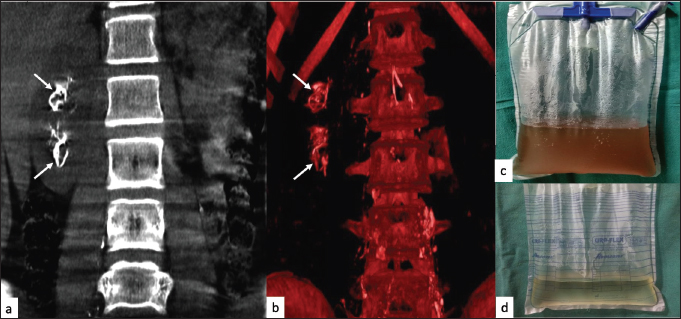

Subsequent CBCT was performed on the DSA table which involved a 240-degree rotation of an X-ray tube around the patient and the acquisition of computed tomography-like images in orthogonal planes. It demonstrated multiple abnormal lymphatics around the right pelvicalyceal system with lipiodol contrast within the right pelvicalyceal system, which strongly suggested a right-sided lympho-pelvicalyceal fistula (Figure 2a and b). The patient was followed conservatively for a week to look for the therapeutic effect of lipiodol, but no improvement in chyluria was seen.

He underwent a cystoscopy which confirmed milky urine from the right ureteric orifice only, with the placement of the right ureteric catheter. RPIS was performed only on the right side using 0.2% povidone-iodine (total daily dose of 5–6 ml) for three consecutive days three times a day. Post-completion of 3rd instillation of povidone-iodine, he had a clearance of urine turbidity (Figure 2c) and complete clearance on day three (Figure 2d). He didn’t complain of any flank pain, nausea, vomiting or fever post-RPIS.

Figure 2. CBCT in coronal (a) plane and volume rendering (b) confirming lipiodol within the right renal pelvicalyceal system (white arrows). (c) Clearance of urine turbidity after the third installation of RPIS. (d) Complete clearance of urine on the third day of RPIS.